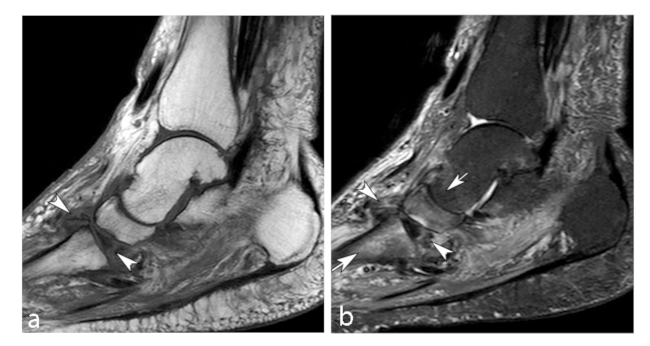

La ON de rodilla afecta a los cóndilos femorales y platillo tibial, denominándose enfermedad de Ahlback cuando se presenta de forma espontánea debido a osteoporosis e insuficiencia subcondral.11 Se presenta alrededor de los 60 años, con frecuencia en el sexo femenino en una relación 3 a 1. El cóndilo femoral interno es el sitio más frecuente afectado debido a ser un área de carga, siendo generalmente unilateral.

Está asociada al consumo de corticoides, suele ser bilateral y en pacientes más jóvenes.5 La afectación de las mesetas tibiales es poco frecuente.

Los primeros estadios de la lesión se caracterizan por una fractura subcondral sin asociación de hallazgos osteonecróticos, reconocida en RM por una imagen lineal de baja señal ponderada en T1, subcortical, y edema periférico extenso mejor evidenciado en secuencias ponderadas en T2. Al avanzar su estadio, estas lesiones osteonecróticas muestran cambios distales por una cicatrización deficiente, lo que genera reacción y formación de cartílago con tejido fibroso indicativo de retraso o falta de unión.11

En RM en secuencia ponderada en T1, la intensidad de señal de la grasa de la médula ósea del cóndilo femoral afectado es reemplazada por un área con baja señal, asociada a una periferia de aún más baja señal (►Figs. 4 y 5).8 En la secuencia ponderada en T2 se visualiza lesión central hipointensa con área de señal alta periférica en relación al patrón de edema de la médula ósea (►Fig. 6).11

Tiene un buen pronóstico cuando el segmento que se afecta es pequeño o el tratamiento es adecuado (descarga completa de la pierna afectada asociado a analgésicos). En caso contrario, evoluciona a una artrosis grave de rodilla con dolor mecánico invalidante. El hallazgo que más influye en la evolución, es el volumen de la zona condílea de carga que se ha afectado, siendo un pronóstico desfavorable al afectarse >50% del tamaño con tendencia al colapso óseo y artrosis secundaria.5,11